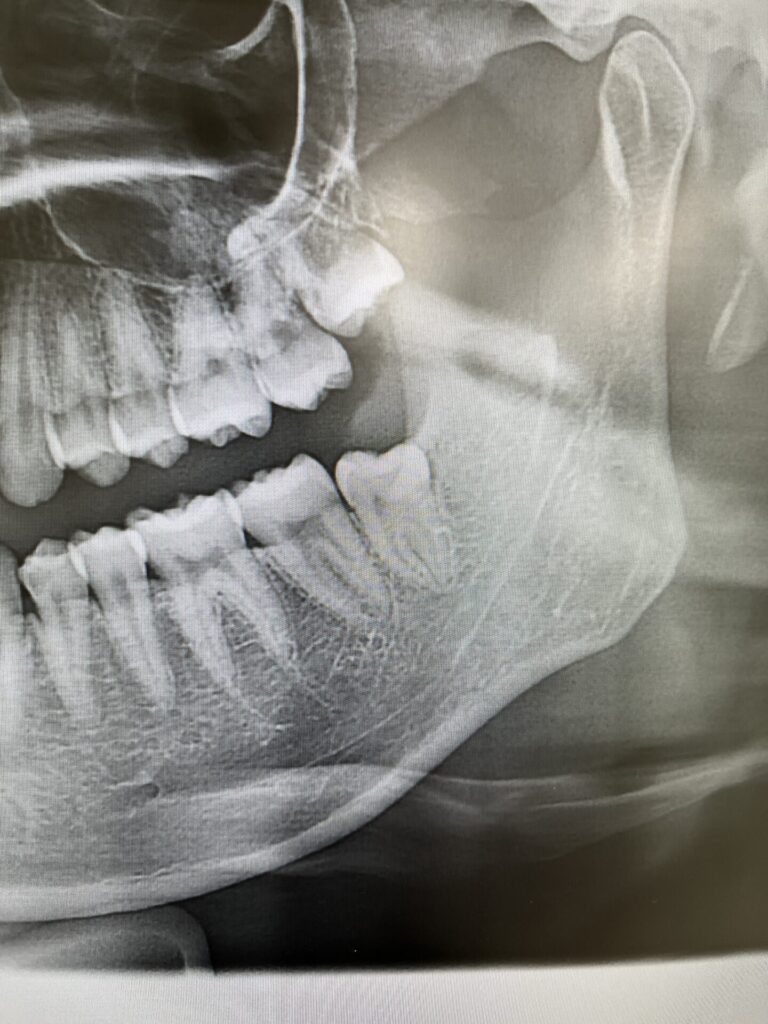

本日の親知らず

本日の親知らずです。

反対側はお茶の水の東京医科歯科大学まで他の病院ではご紹介で出向いていたらしく、今回はそこまで通う時間がなかなか取れないとのこと。

上の親知らずは完全に埋まっており埋伏抜歯でありましたが、スムーズに抜歯。特に問題も出ず終了いたしました。